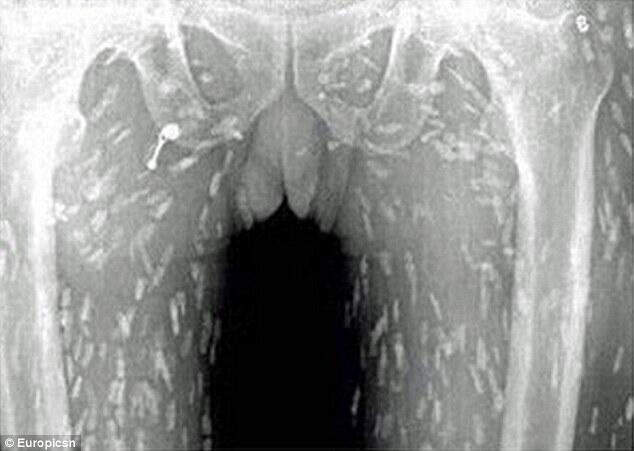

To his horror, scans revealed his entire body had been infected with tapeworm after eating too much sashimi - raw slices of fish.

Doctors believe some of the uncooked Japanese delicacy of raw meat or fish must have become contaminated.

He was treated at the Guangzhou No. 8 People's Hospital in Guangdong Province, in eastern China.

Dr Yin, of Guangzhou No. 8 People’s Hospital, told the website that'smags.com that eating uncooked food contaminated with tapeworms' eggs could eventually cause cysticercosis, when the adult worms enters a person’s blood stream.

This type of infection is life-threatening once it reaches the brain.